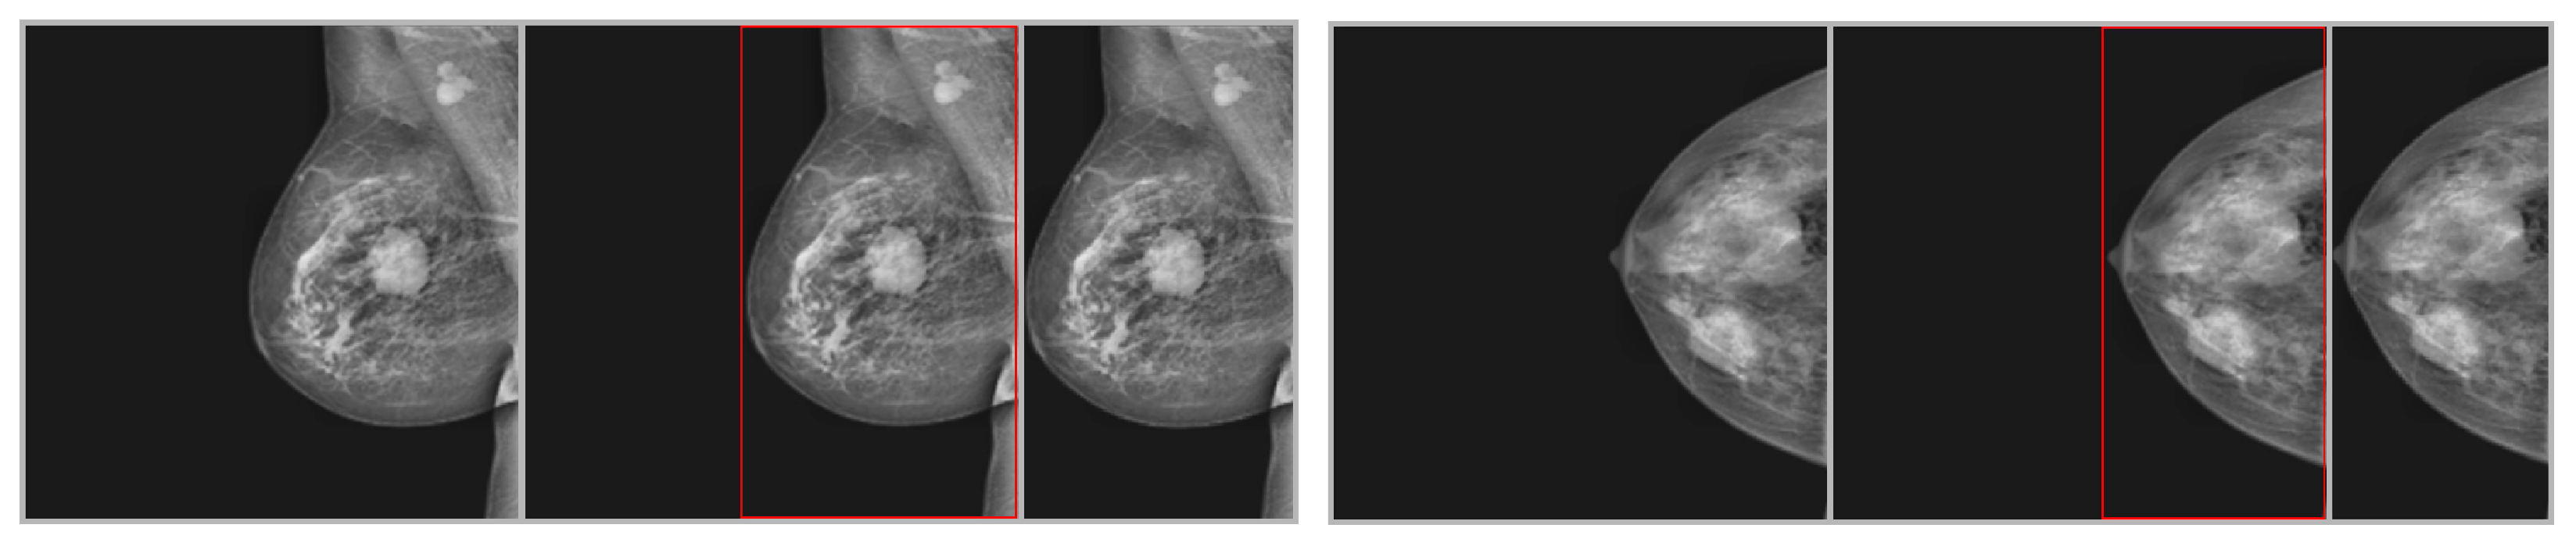

Pixel values were normalized through the z-scoring technique after cropping [44]. Since the number of slices was not constant among the different patients and image types, a nearest-neighbor resampling technique was employed to achieve a consistent 30 slices for each image type and case. Image cropping was performed using Python v3.13.2 and Scikit images v1.1. Though z-scoring and fast nonlocal denoising techniques were executed using Python and OpenCV (version 0.16.1), the complete preprocessing of available images was performed automatically. All images were obtained from the same session and position, so there was no need for co-registration of different sequences for this research. The output of cropping is shown in Figure 4.

Figure 4.

Steps of cropping the ROI for two sample images from the INbreast dataset. The first image is an input image, the second is a detected ROI, and the third is a cropped image.